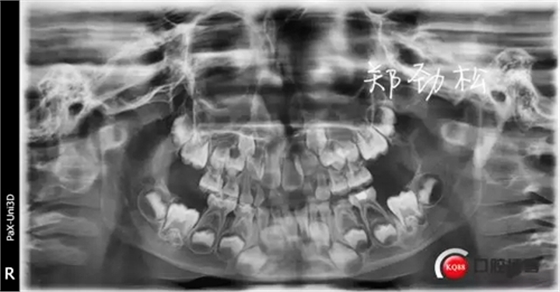

病例一

主訴:牙齒反復發(fā)炎近一年

現(xiàn)病史:患兒父親代述一年前患兒前牙在外院做過根管治療,后前牙唇側牙齦反復膿腫前來就診。

檢查:7A牙體變色,舌側有充填物,叩診(++),松一度,冷熱刺激無反應,唇側牙齦紅腫有一瘺管。

診斷:7A慢性根尖炎

處置:開隨,去除根充物后沖洗引流。

此病例術后取出根充物發(fā)現(xiàn)其中有兩根牙膠尖,其實大家都知道乳牙的牙根隨著恒牙的萌出會逐漸吸收,而牙膠尖不能被吸收,所以牙膠尖不能夠用作乳牙根充,我常規(guī)選擇vitapex糊劑作為乳牙的根充材料。